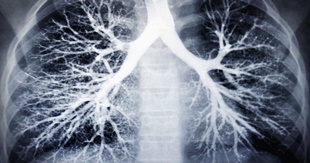

흉부X선 검사와 늑막 생검으로 진단이 가능해요. 청진시 호흡음이 감소되거나 가슴을 두드렸을 때 둔탁한 느낌이 들기도 합니다. 진단에 명확하지 않은 경우 흉강내시경을 이용하기도 해요.